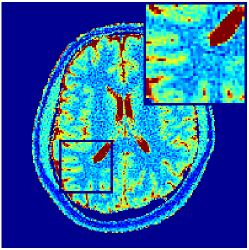

According to [44] as we progress into deeper layers, partitions will be subdivided into smaller segments in a hierarchal fashion. This can be observed in Figure 2 where we adopted the above routine for the T1/T2 encoding MRF sequence used in our experiments and visualised multi-scale (from coarse-to-fine) partitions obtained after each residual layer. The Bloch response manifold is sampled across fine-gridded T1/T2 values (i.e. MRF dictionary) to visualise the intersection of the input space segments with this manifold (results are visualised across the three dominant principal component axes). MRFResnet encoder learns about a thousand partitions for its end-to-end mapping . In the light of (16) we know that for each partition the network implicitly encodes deep matched-filters (the rows of or alternatively ) and an offset term to locally linearly regress the T1/T2 outputs in that segment. As such instead of memorising 100K dictionary atoms used for training, the network learns a compact piece-wise affine approximation to the Bloch manifold projection (5) as a rapid and memory-efficient alternative to DM’s point-wise approximation (7). The total number of parameters used by the MRFResnet (Table I) are two hundreds times less than the size of the dimension-reduced MRF dictionary. Figure 3 shows the Bloch responses for a range of T1/T2 values, as well as deep matched-filters learned by MRFResnet to predict each of these quantities in this range from noisy inputs. Computed through (17), match-filters are one-dimensional analogues of the saliency maps a.k.a. deep dream images [49], measuring sensitivities of the T1/T2 output neurons with respect to the inputs.